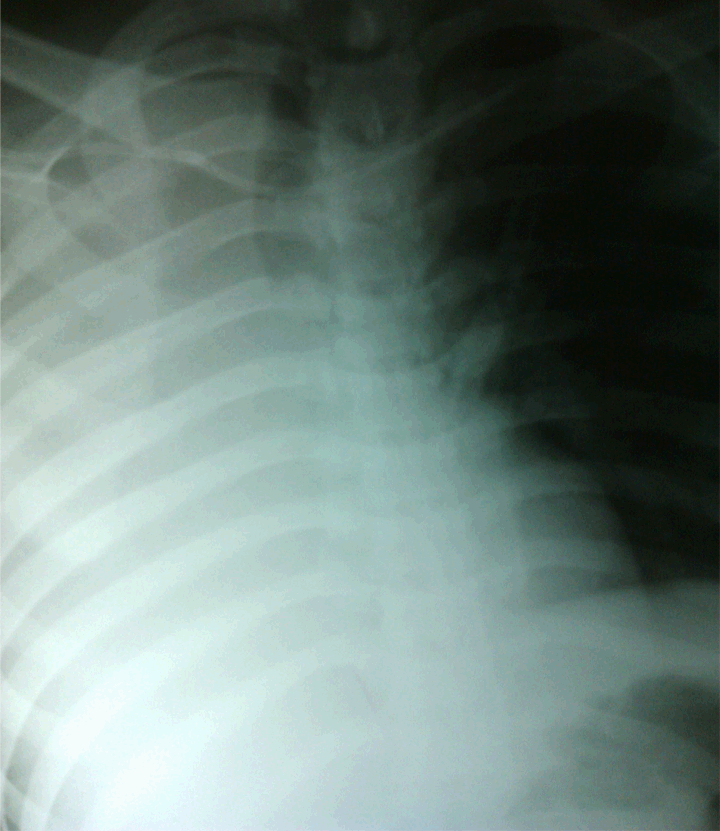

On the following morning, he was noted to be in mild respiratory distress, with a respiratory rate of 24/min, shallow pattern, SpO2: 90% (FiO2: 100% via a Hudson mask with reservoir bag) with marked dullness and reduce air entry on the right chest. His heart rate was 90/min and blood pressure 105/70 mmHg. Laboratory results were: hemoglobin 11.5 g/dL, white blood cell 15x103/µL. A repeat chest X-ray (Figure 2) showed a complete opacification of the right hemithorax.

Cursor on image to zoom/Click text to open image

Figure 2: Total opacification of the right hemithorax misdiagnosed as hemothorax or pneumothorax. Note the tracheal deviation towards the side of opacity, which was suggestive of volume lost of the right hemithorax and thus suspicious of atelectasis.